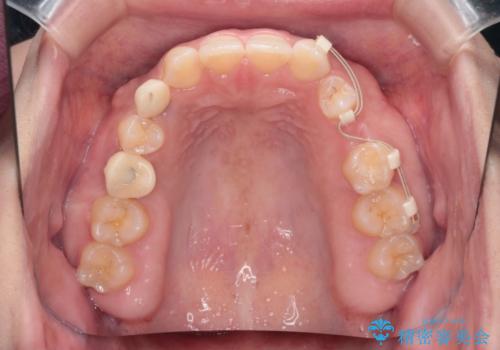

- 後続永久歯が欠損した患者様です。

矯正治療にて歯並びを改善したのち、インプラントにて咬合回復を行う治療計画としました。

捻転が強い部分だけはワイヤーの部分矯正で対応しております。